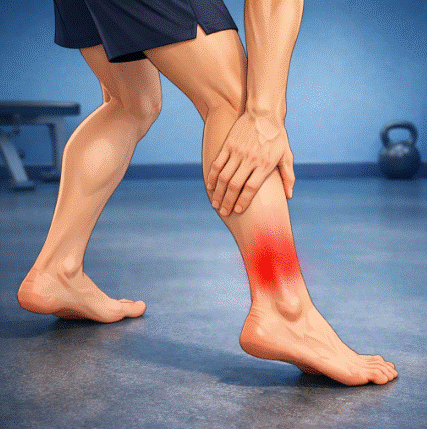

Terapia manual en tendinopatías: evidencia y abordaje multimodal

La terapia manual en tendinopatías ha sido durante años relegada a un papel secundario en los protocolos de tratamiento, donde el ejercicio terapéutico —especialmente el excéntrico— acaparaba prácticamente toda la atención clínica y científica. Sin embargo, una perspectiva clínica publicada en 2022 en el Journal of Manual and Manipulative Therapy por Jayaseelan, Sault y Fernández-de-las-Peñas […]